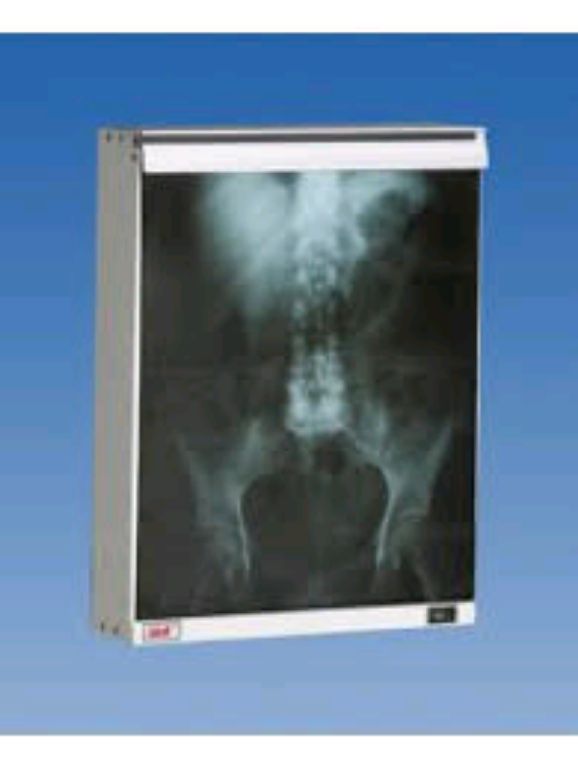

The X-ray view box is a device consisting of lights mounted behind a transparent screen and used to provide a radiographic image with backlighting. This lets clinicians see an image’s light, contrast, and details. It is also identified as an illuminator.

- Condition: New

- Lightweight and portable

- Durable construction